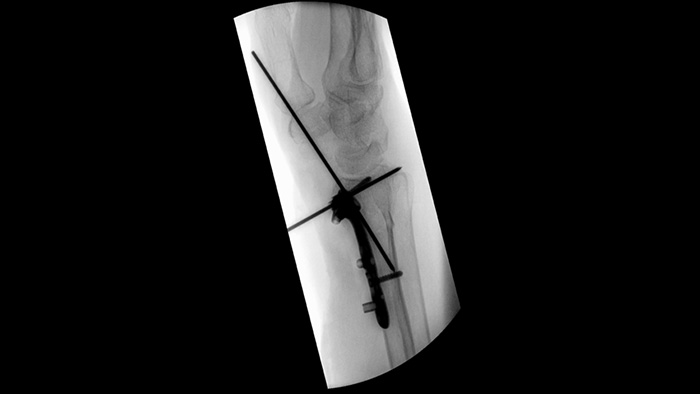

Simplifique o fluxo de trabalho para casos ortopédicos desafiantes que exijam um reposicionamento frequente do arco em C móvel. Com a memória de posição2, os participantes num estudo de usabilidade1 alcançaram um reposicionamento 94% correto à primeira e sentiram menos frustração durante as tarefas de reposicionamento.

Os obturadores assimétricos únicos aumentam a flexibilidade da colimação e ajudam a colimar a anatomia utilizando uma colocação independente do obturador com um dedo. Pode ajustar os obturadores e a orientação da imagem enquanto está na última imagem adquirida sem utilizar radiação.